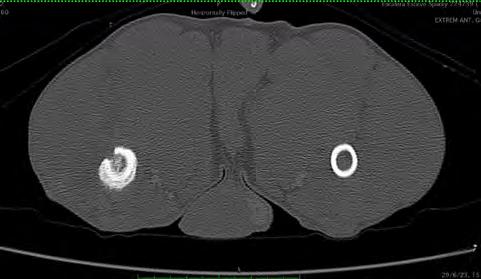

En la diáfisis media y metáfisis distal del fémur derecho, se visualizó una lesión ósea con características agresivas (Fig. 1). Presentaba un aumento de atenuación de la cavidad medular del hueso, heterogénea, y una reacción perióstica sólida y con “borde de cepillo” que rodeaba de forma concéntrica el fémur. Esta lesión

1. (A) Imagen de TC en ventana hueso en un corte transversal. En la sección femoral de la extremidad pelviana derecha se observa una lesión agresiva con reacción perióstica y aumento de la atenuación medular. Se aprecia asimismo un defecto cortical presumiblemente causado por la biopsia ósea realizada previamente. (B) Imagen de TC en ventana hueso reconstruida en plano dorsal. En el fémur derecho se visualizan las lesiones óseas descritas en (A). (C) Imagen de TC en ventana hueso reconstruida en plano sagital. Se observa la lesión ósea de características agresivas y el defecto cortical descrito en (A). Caudodistalmente al defecto óseo provocado presumiblemente durante la biopsia, se intuye una estructura redondeada ligeramente hiperatenuante respecto a los tejidos adyacentes compatible con el pseudoaneurisma descrito en este caso.

era compatible con un proceso neoplásico óseo primario o metastático (osteosarcoma o sarcoma histiocítico), ocon un proceso infeccioso (fúngico o menos probablemente otros como leishmaniosis o hepatozoonosis). En la cortical laterocaudal, se observó un defecto óseo con márgenes bien definidos, probablemente producido por la biopsia descrita en la historia.

En los tejidos blandos junto al aspecto caudodistal del fémur, se visualizó una estructura redondeada, de 3 cm de diámetro y de atenuación líquido/tejido blando en precontraste, con un realce marcado postcontraste sugestivo de estructura vascular (Figs. 2 y 3). La vena y arteria femoral derecha presentaban apariencia normal hasta el aspecto distal del fémur, donde la vena femoral parecía conectar con la estructura descrita. La arteria femoral quedaba en íntimo contacto con dicha estructura, aunque no parecía estar conectada. Este hallazgo era compatible con una dilatación aneurismática afectando a la vena femoral. Distalmente a esta lesión, la arteria y vena poplíteas se observaban ligeramente más distendidas en comparación al lado contralateral. También había un leve aumento de atenuación de la grasa subcutánea de forma difusa distal a la lesión compatible con edema subcutáneo.